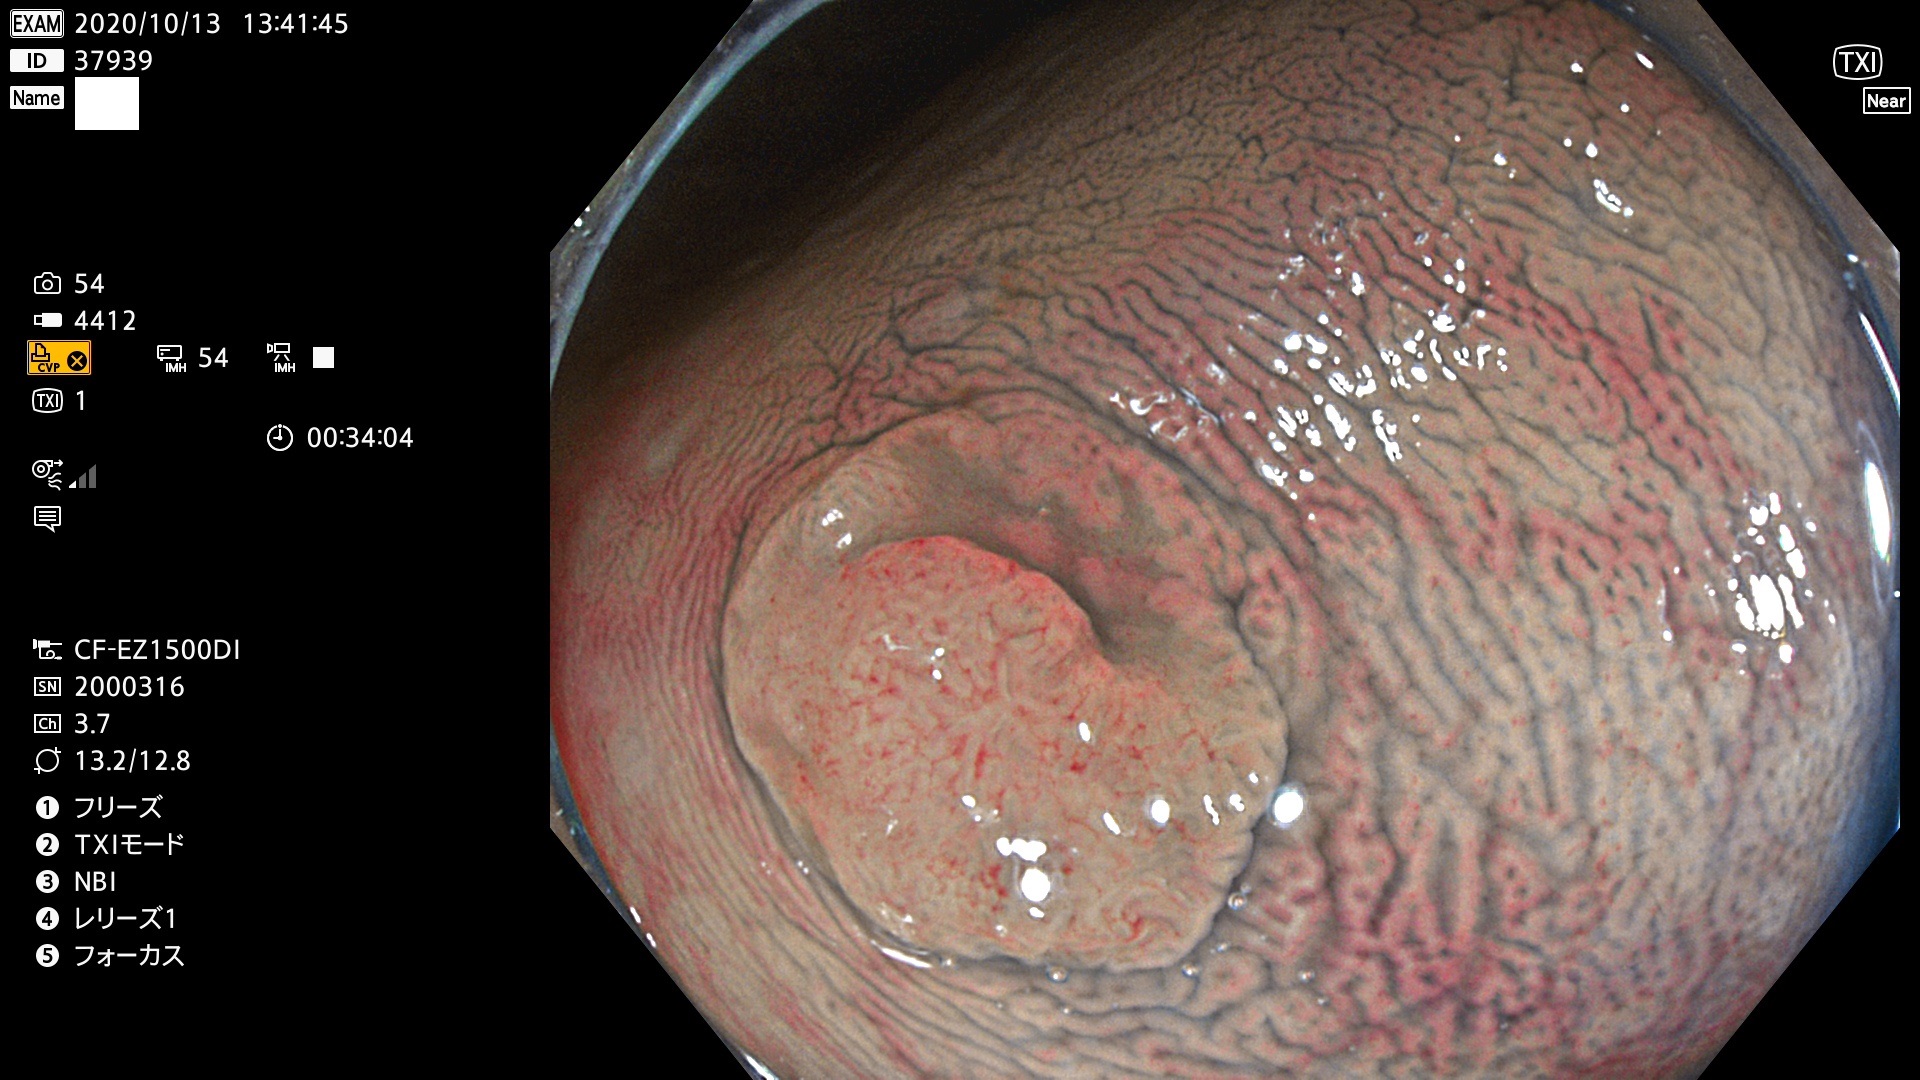

発見困難で危険性の高い平坦型病変(上記100名より抽出)

37900 37902 37903 37904 37905 37906 37907 37909 37910 37911 37912 37913 37914 37915 37916 37917 37919 37921 37922 37923 37926 37928 37929 37930 37931 37933 37934 37935 37936 37937 37938(SSAPのみ) 37939 37940 37941 37942 37943 37946 37947 37948 37949 37951 37952 37953(SSAPのみ) 37955 37956 37957(SSAPのみ) 37958(SSAPのみ) 37960 37962 37963 37964 37966 37967 37968 37971 37972 37973 37975 37976 37977 37979 37982 37983 37984 37985 37986 37987 37988 37989 37990 37991 37992 37993 37994 37995 37996 37998 37999